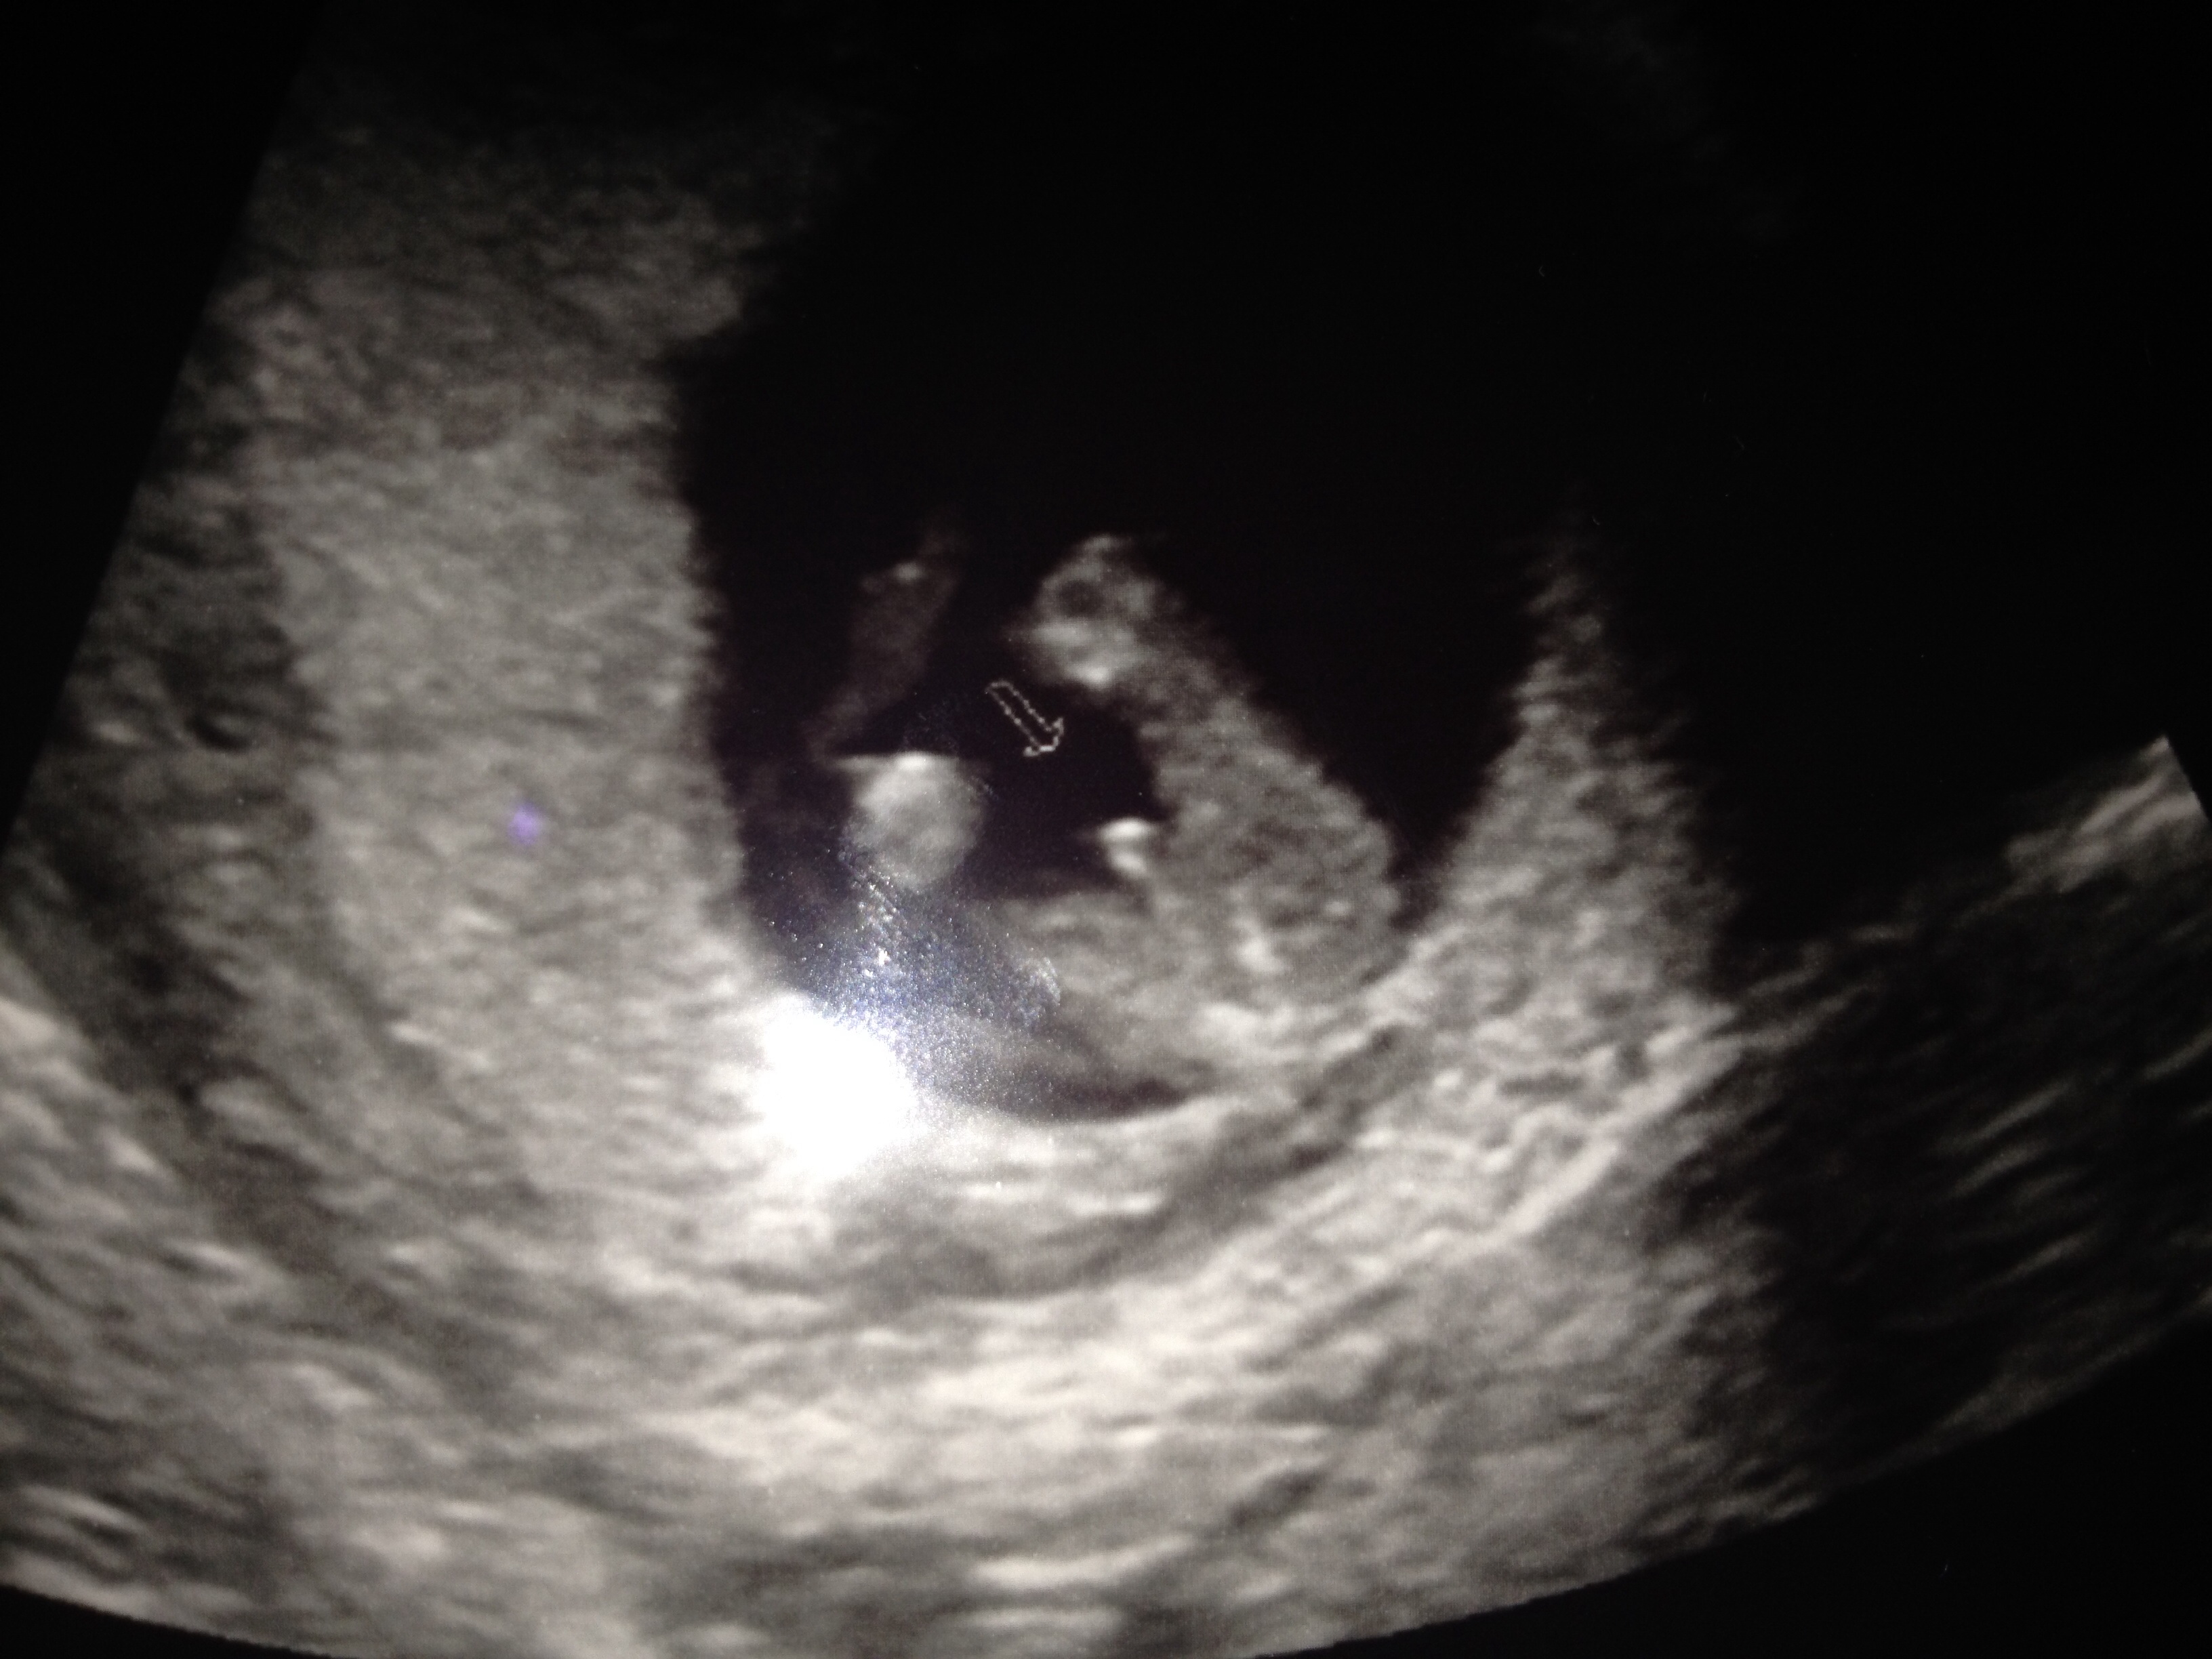

Had 13 week scan yesterday and tech said he thinks a boy, positive enough to get excited but not to start buying things. What do you guys think?? Could this be the longed for boy??? Have only got potty shot as couldn't get decent side view!!Attachment 19956Attachment 19956Attachment 19956